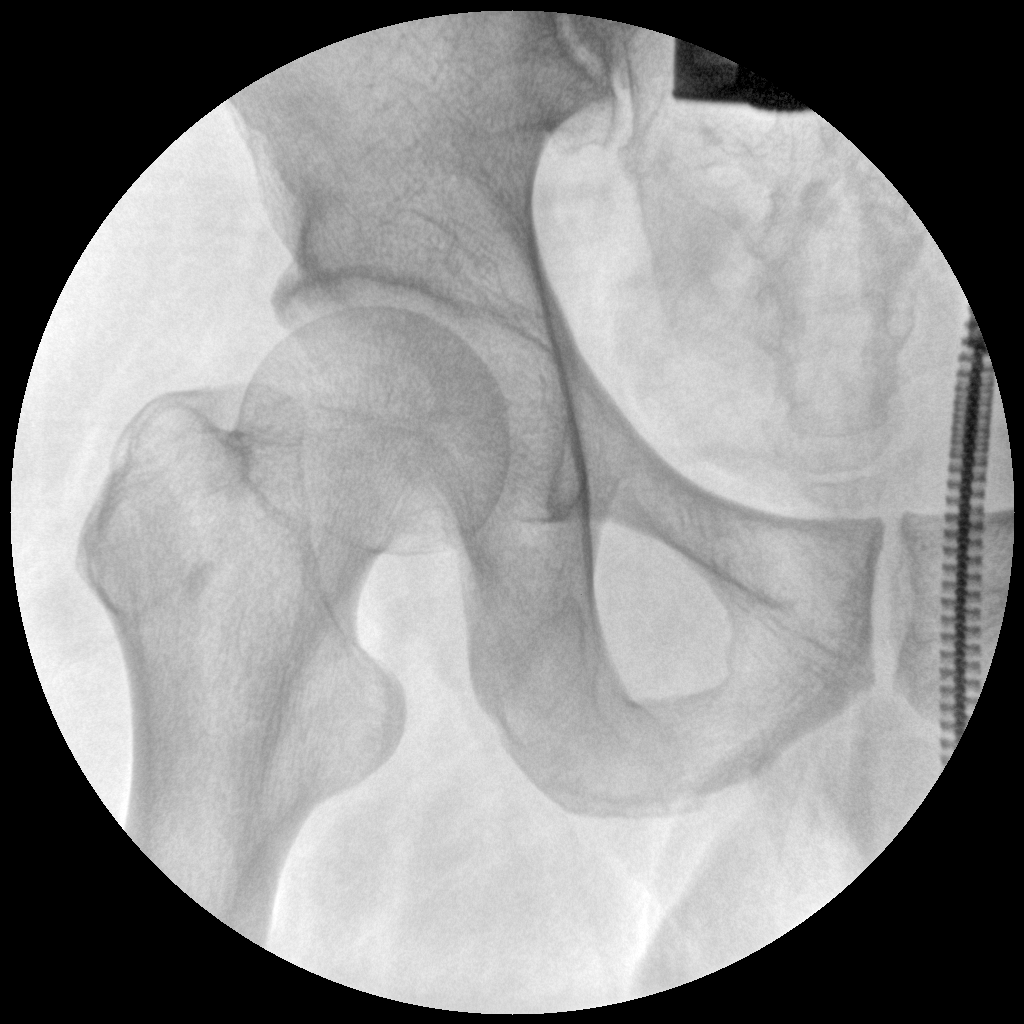

Clinical picture

臨床圖片